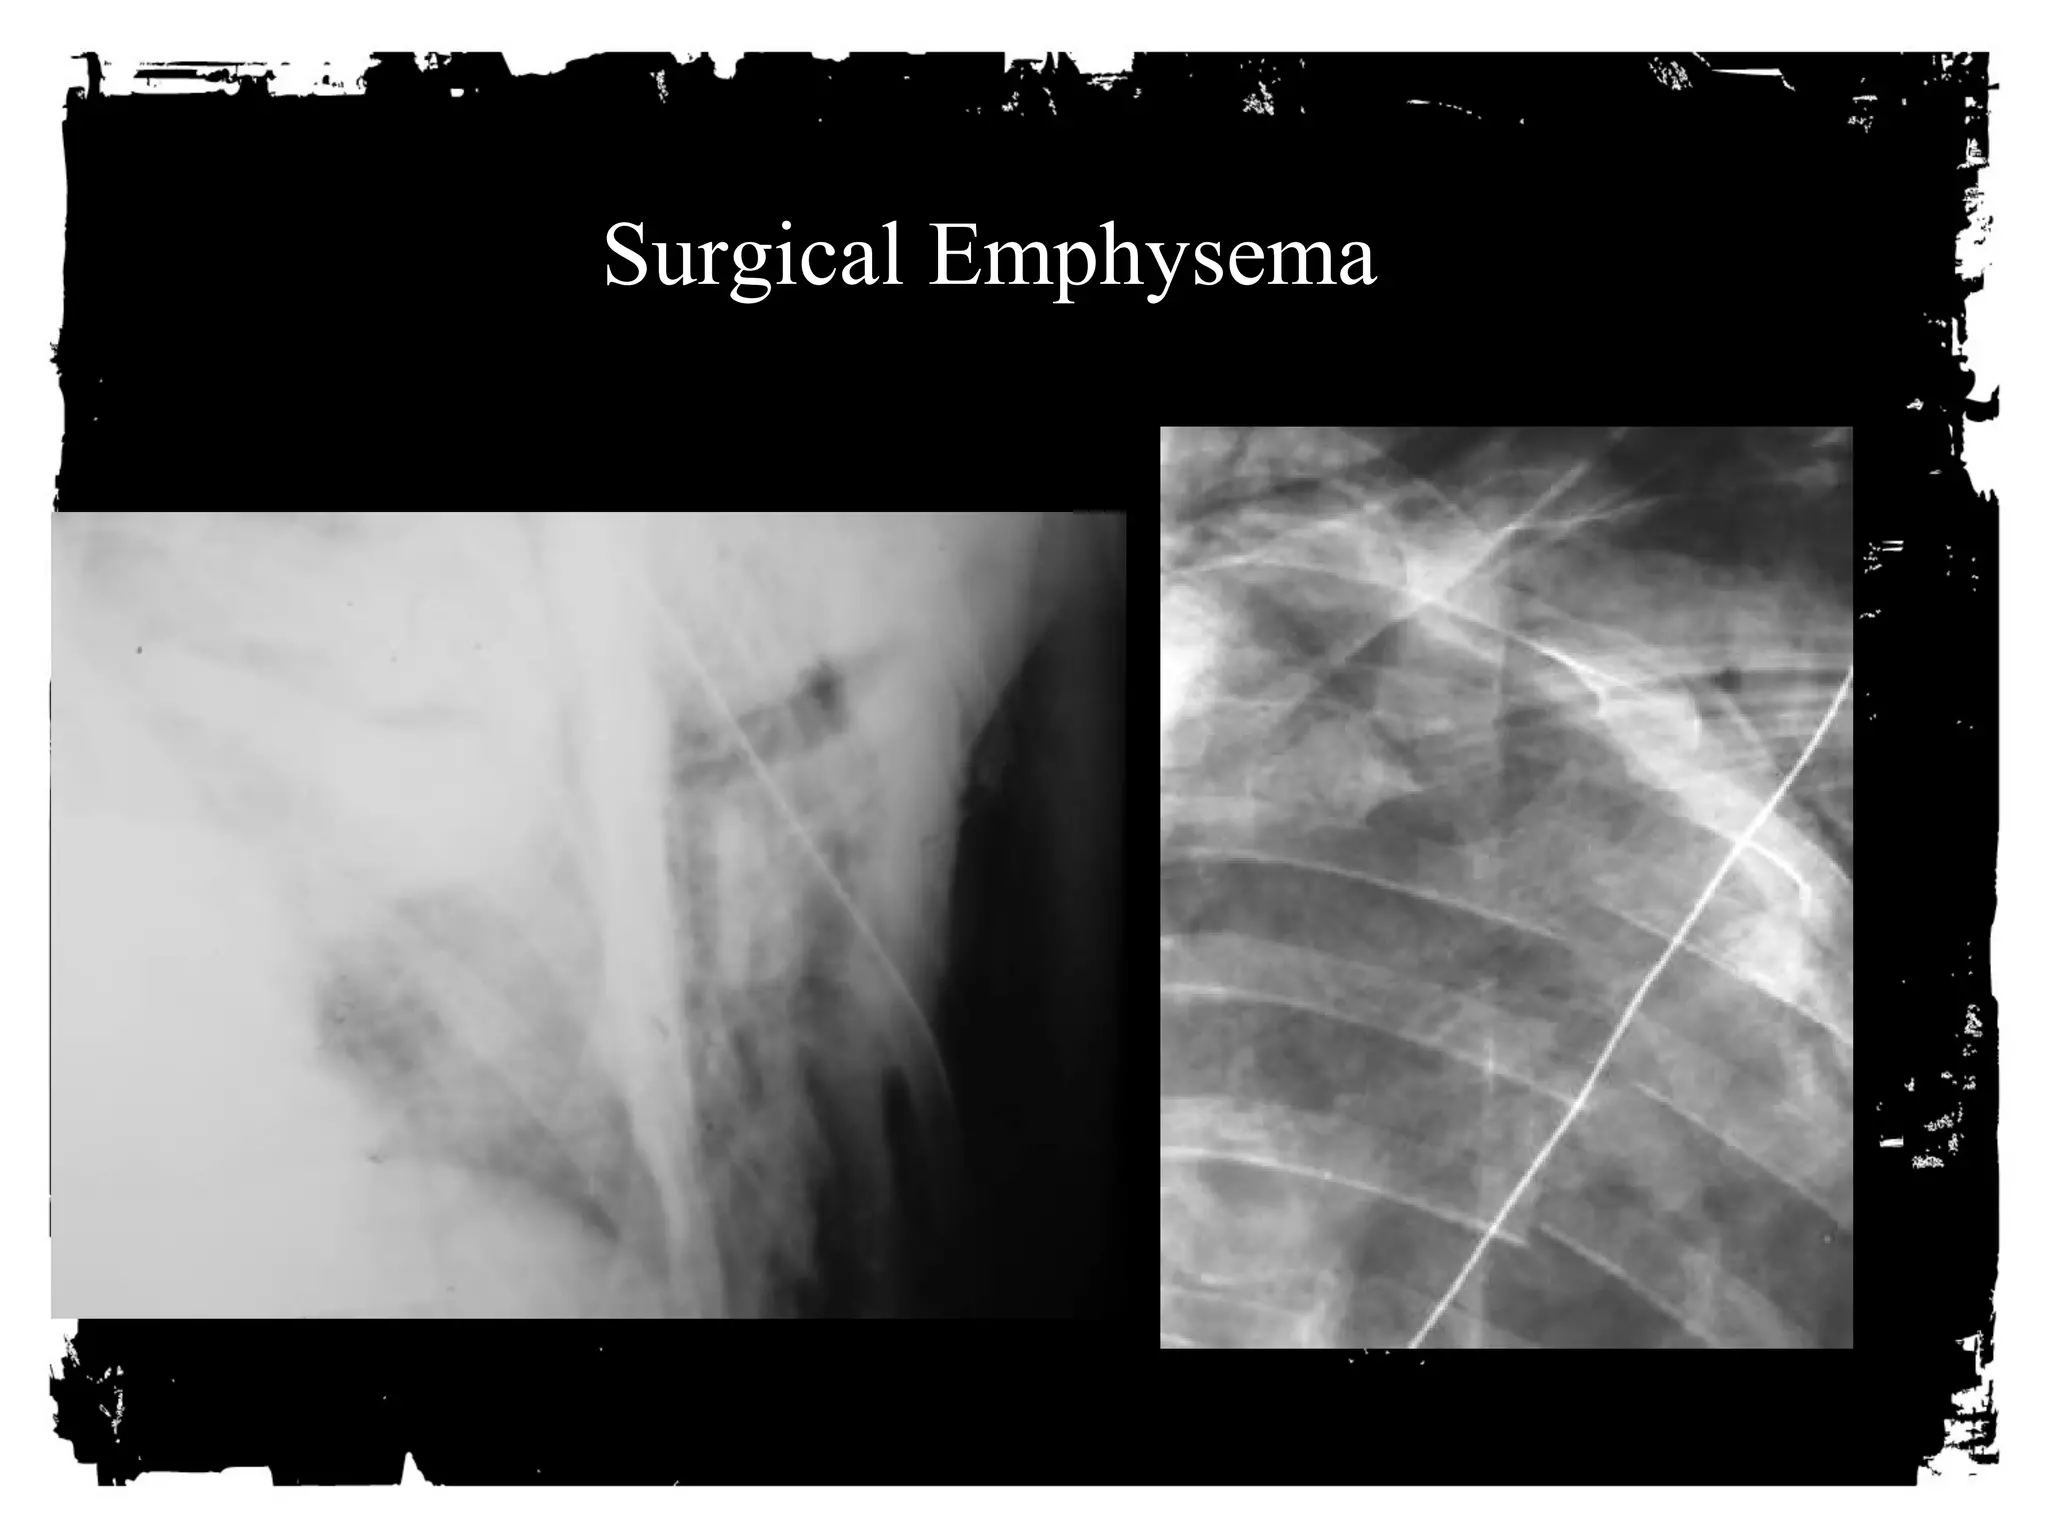

AIR where it shouldn’t be

• Pneumothorax

• Pneumomediastinum

• Subcutaneous emphysema

• Systemic venous air embolism

• Pneumopericardium

• Pneumoperitoneum/retroperitoneum

PNEUMOMEDIASTIUM

• Usually from ruptured alveoli.

• Can also be from trachea,

bronchi, esophagus, bowel and

neck injuries.

CLICK HERE PNEUMOMEDIASTIUM

TO ADD TEXT

Signs:

• Linear paratracheal lucencies

• Air along heart border

• “V” sign at aortic-diaphragm

junction

• Continuous diaphragm sign

Surgical Emphysema